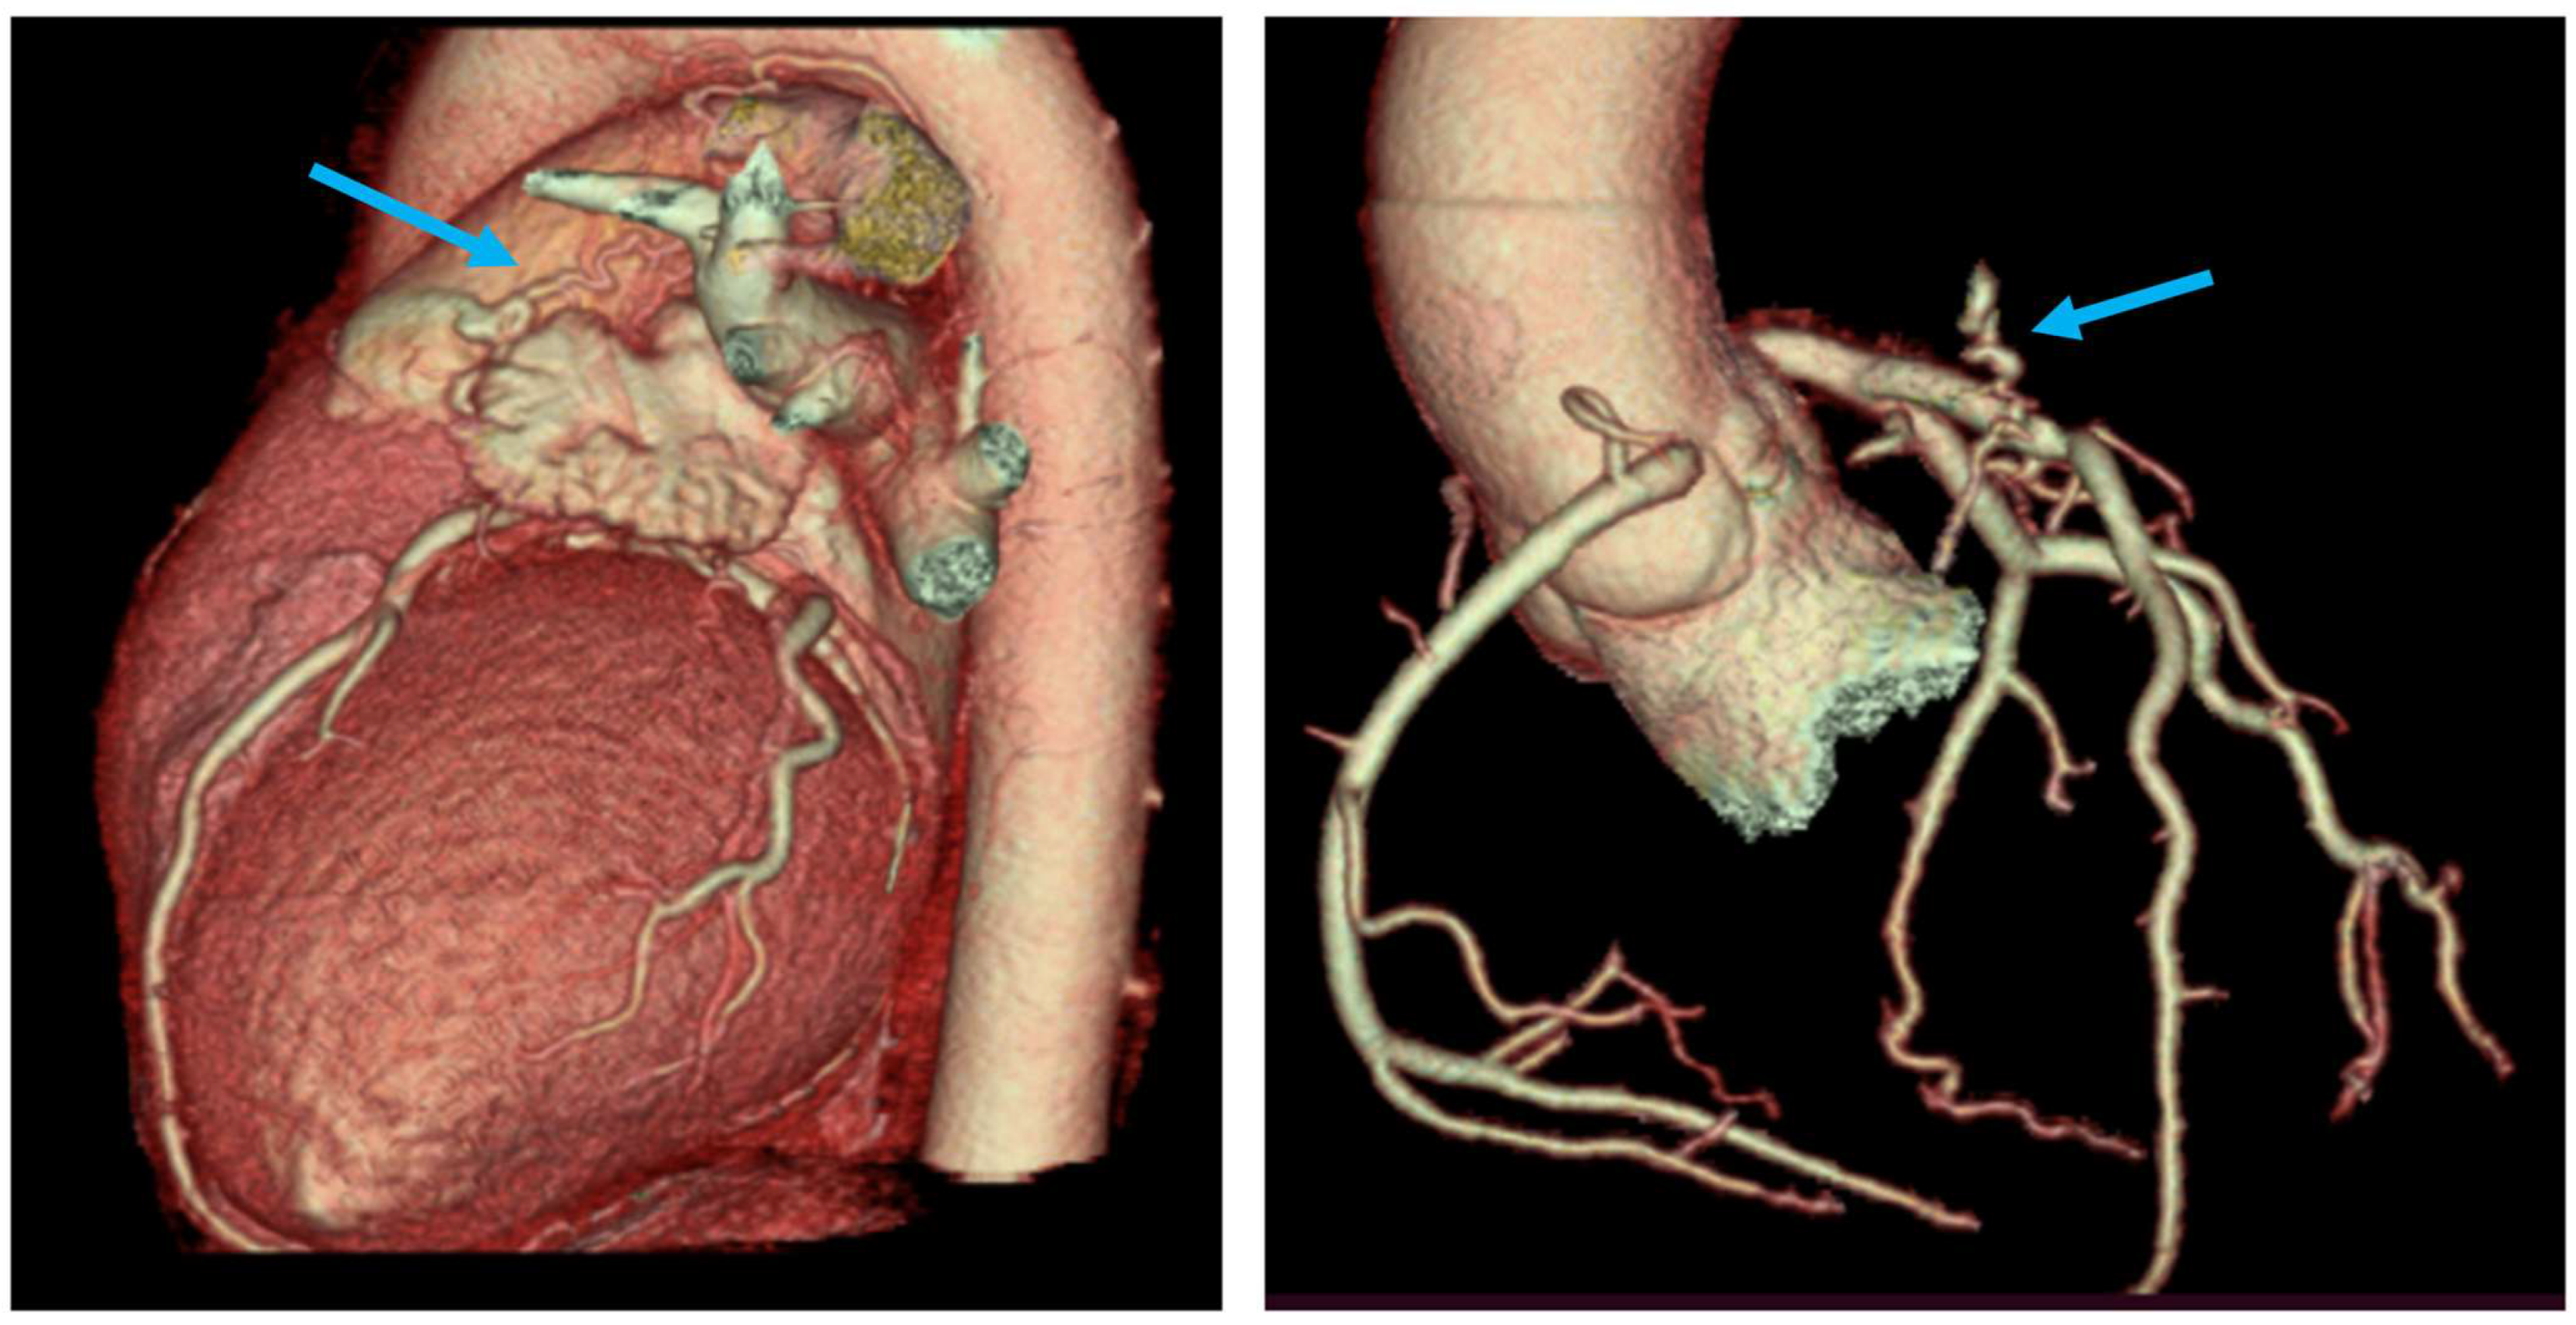

- Type A—proximal coronary dilation at the origin of fistula and normal distal end;